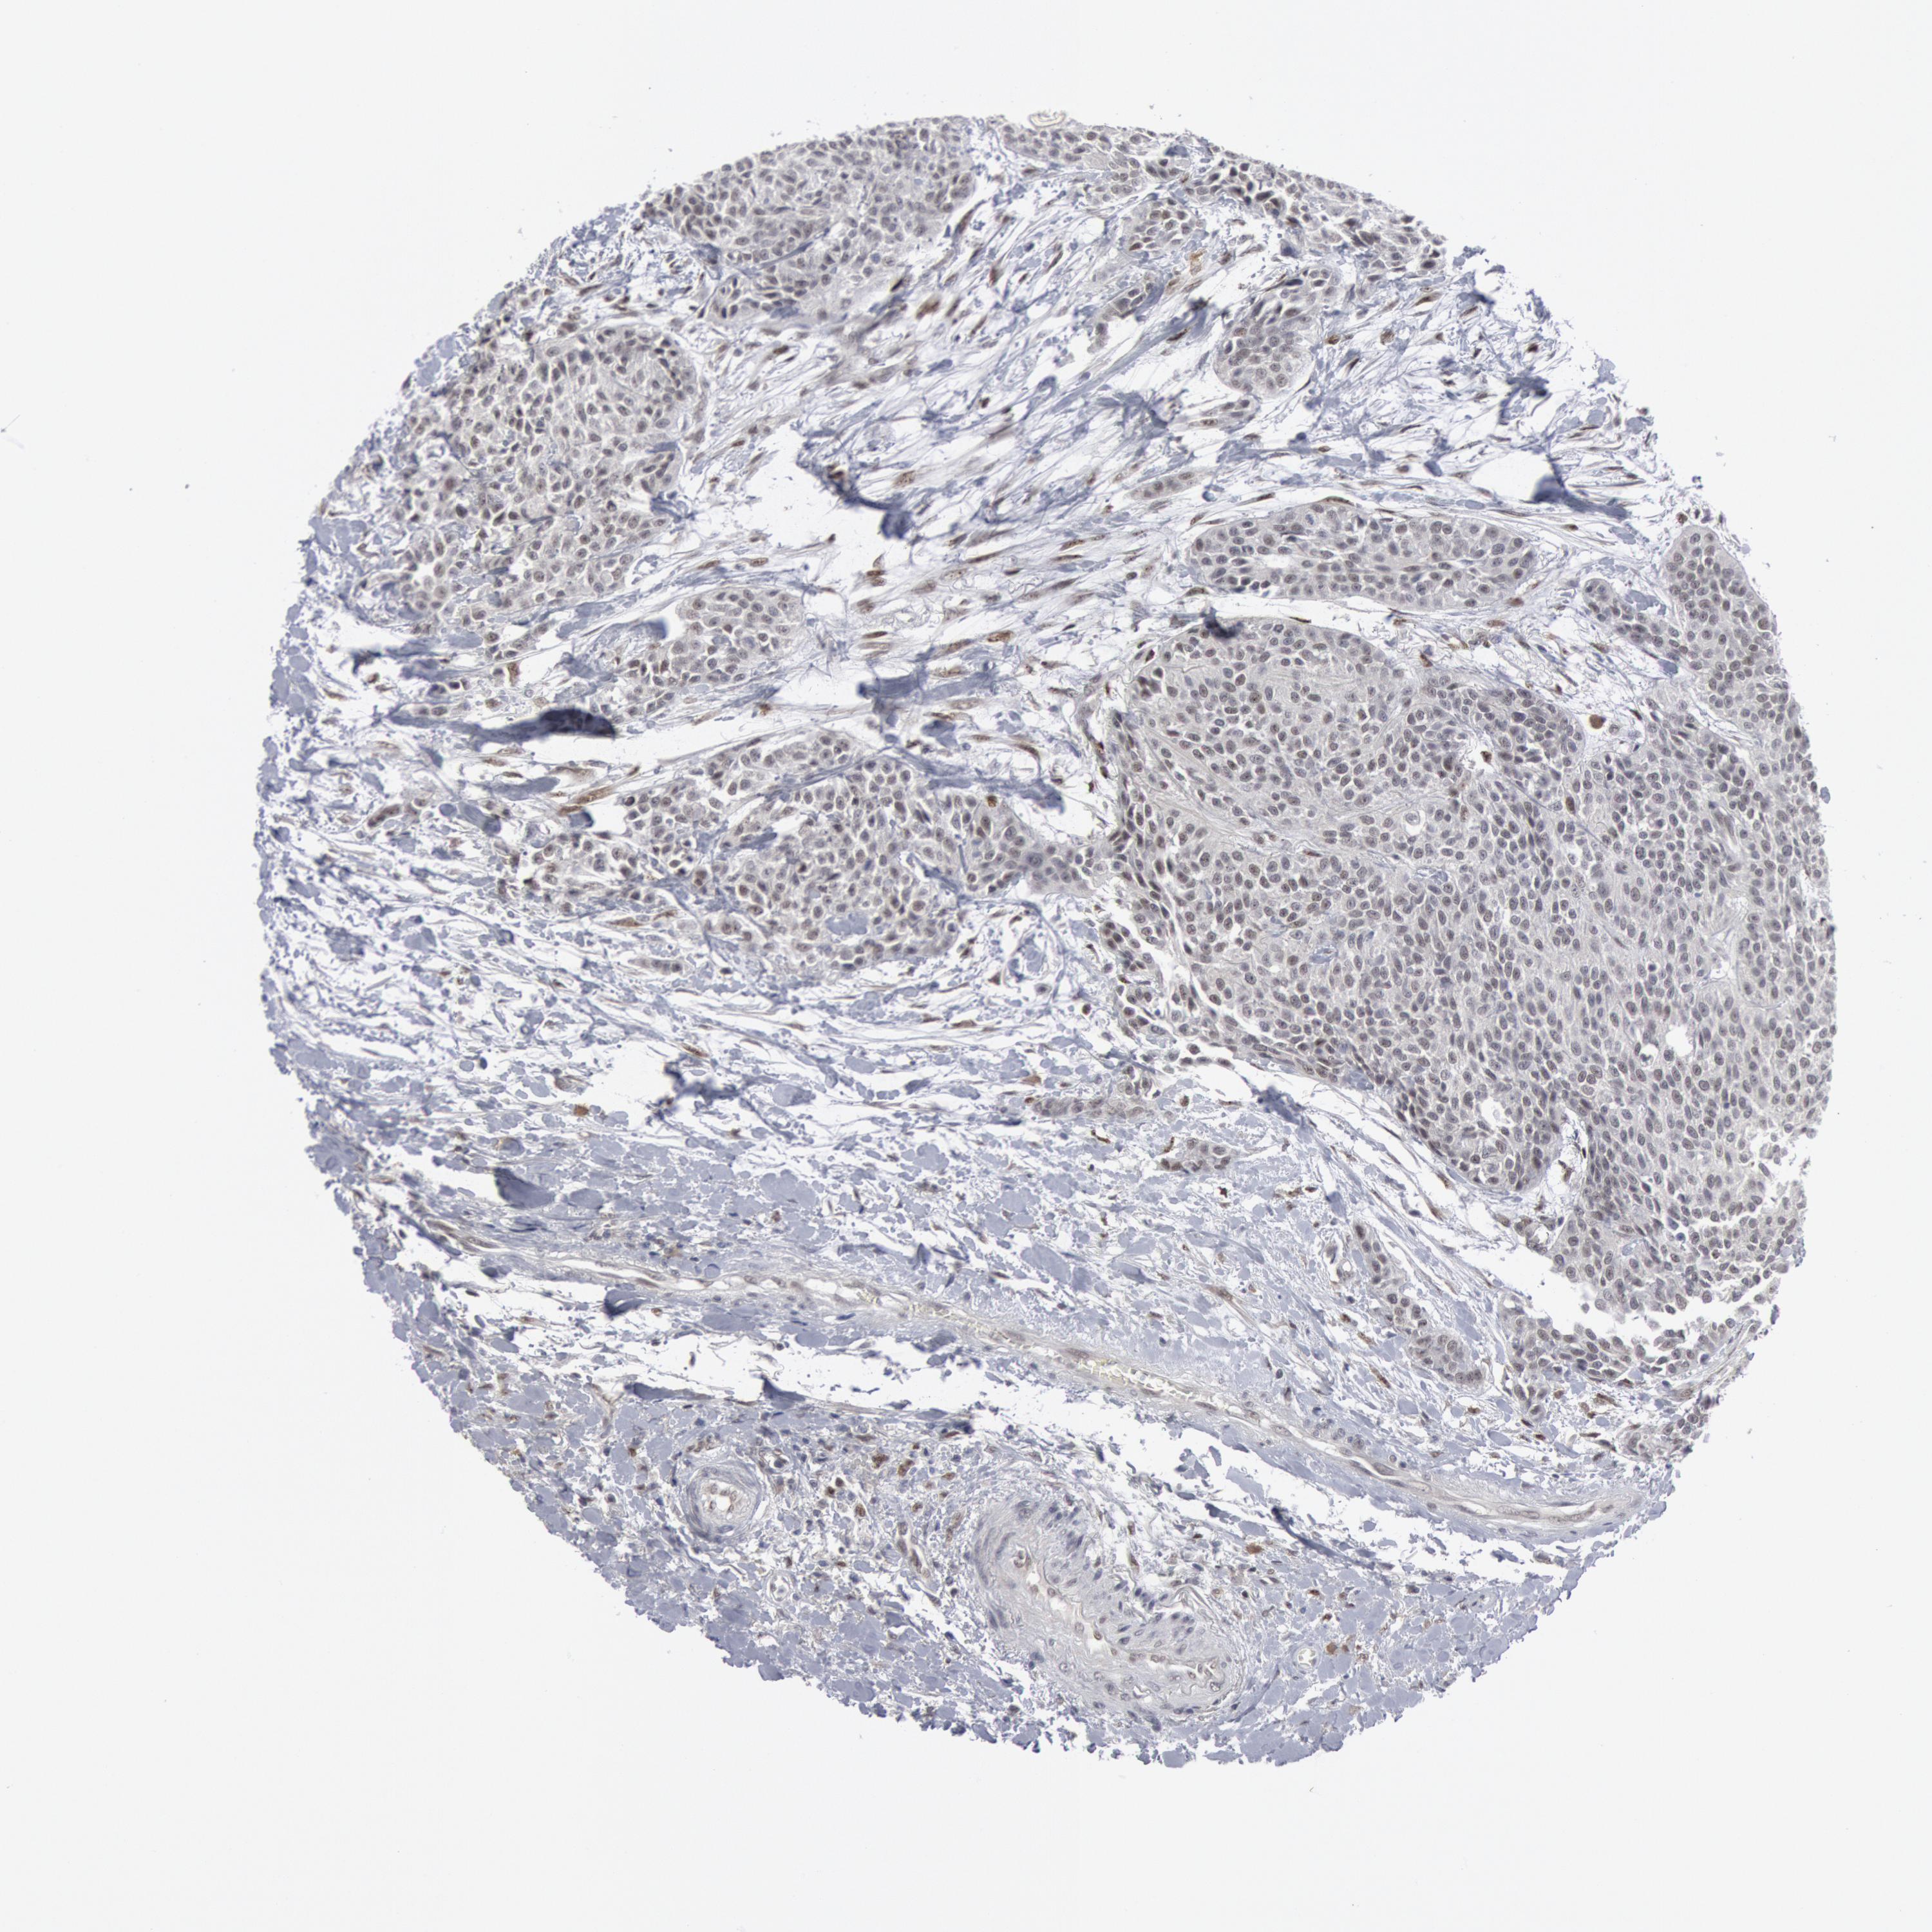

UROTHELIAL CANCER - Protein expressioni

A mouse-over function shows sample information and annotation data. Click on an image to view it in a full screen mode. Samples can be filtered based on level of antibody staining by selecting one or several of the following categories: high, medium, low and not detected. The assay and annotation is described here.

Note that samples used for immunohistochemistry by the Human Protein Atlas do not correspond to samples in the TCGA dataset.

Antibody stainingi

Antibody staining in the annotated cell types in the current human tissue is reported as not detected, low, medium, or high, based on conventional immunohistochemistry profiling in selected tissues. This score is based on the combination of the staining intensity and fraction of stained cells.

Each image is clickable and will lead to virtual microscopy that enables deeper exploration of all samples and also displays staining intensity scores, fraction scores and subcellular localization as well as patient and tissue information for each sample.

HPA001252

Urothelial carcinoma, High grade

Urothelial carcinoma, Low grade

Adenocarcinoma, NOS